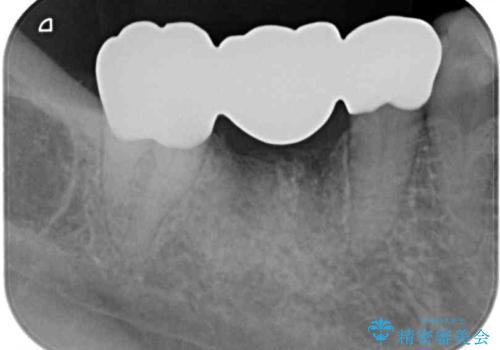

ただし、インプラント以外にブリッジでの補綴治療も可能であったので、抜歯後に治癒を待って、フルジルコニアブリッジにて補綴することとしました。

インプラント治療が回避でき、前後の銀歯も合わせてセラミックにできたので、患者様には大変満足していただきました。